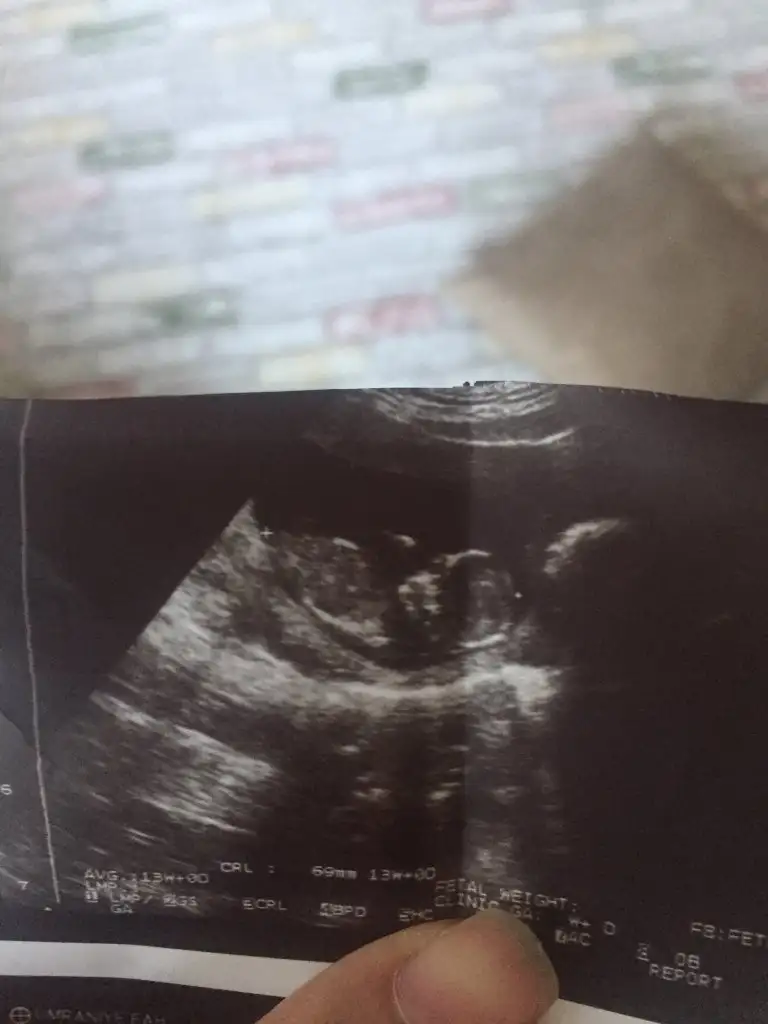

Merhabalar, ctesi ikili test icin gittim 11+6 idim. Suana kadar hep haftayla uyumlu giderdi sat. Ama bu sefer 12+6 cıktım. Yine de cinsiyet yorumlar mısınız? Gec mi kaldım? Bir de doktor tahminini söyledi ama emin değil. Kafanız karışmasın diye en son söyleyeceğim.

Eklentiler

• 3DD5B10D-76F7-458F-AC69-6E5F948B3560.webp

3DD5B10D-76F7-458F-AC69-6E5F948B3560.webp

23,2 KB · Görüntüleme: 58

Bir de bunu verdi doktor. Sanırım bacak arası ve kenardakiler de bacakları burada. 11+6 idim.